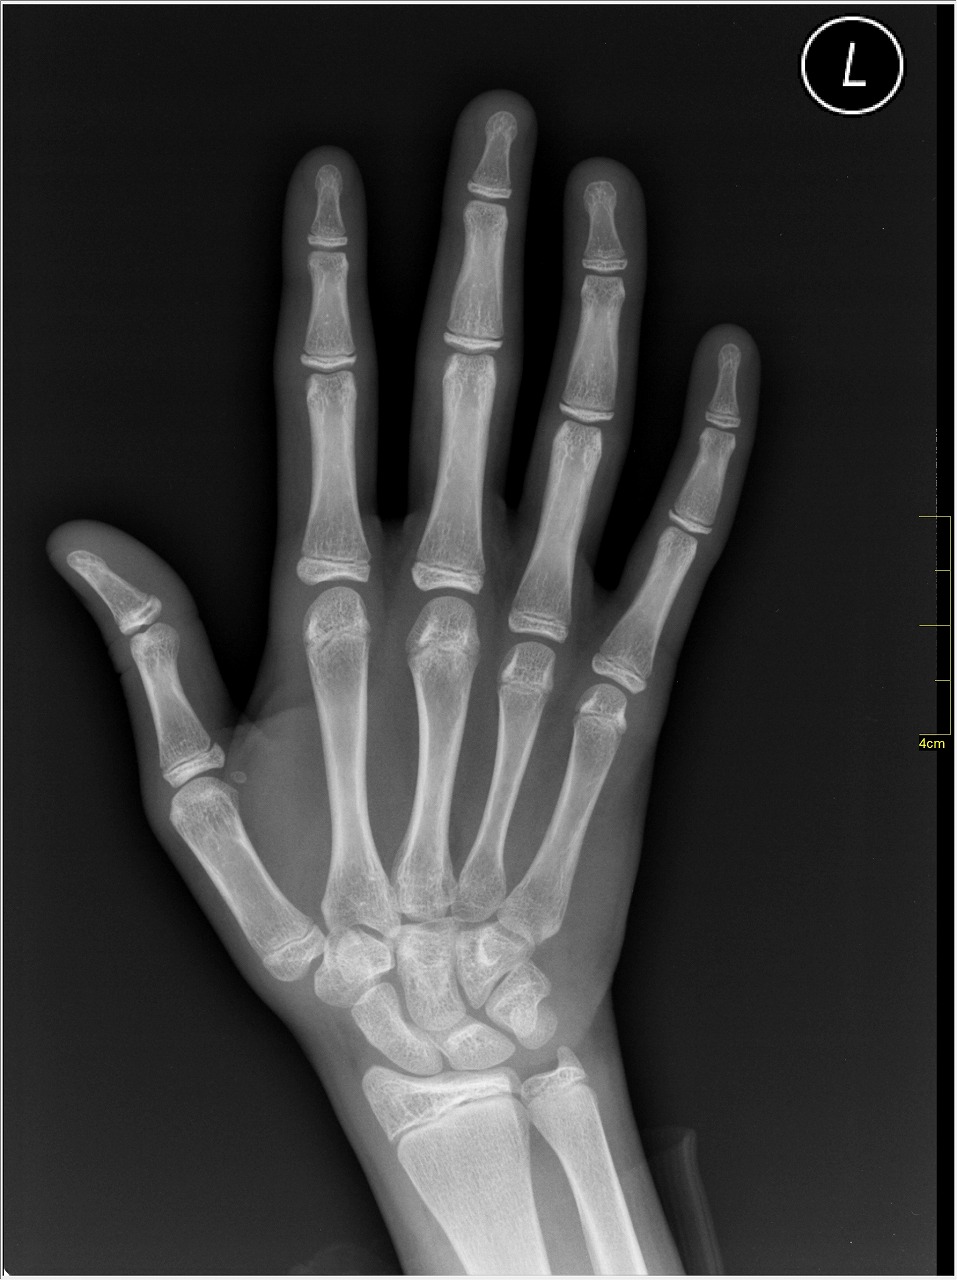

实验4结束后(一对上肢消失)D-81131401肩部X光照片

结果:一对上肢消失。

备注:无注意事项。其影响同样波及了骨骼。虽然这导致受试者的运动器官严重缺损,但其并未报告运动有障碍。其仍然宣称“自己的身体本身就是这样,是实验负责人员身体畸形”。